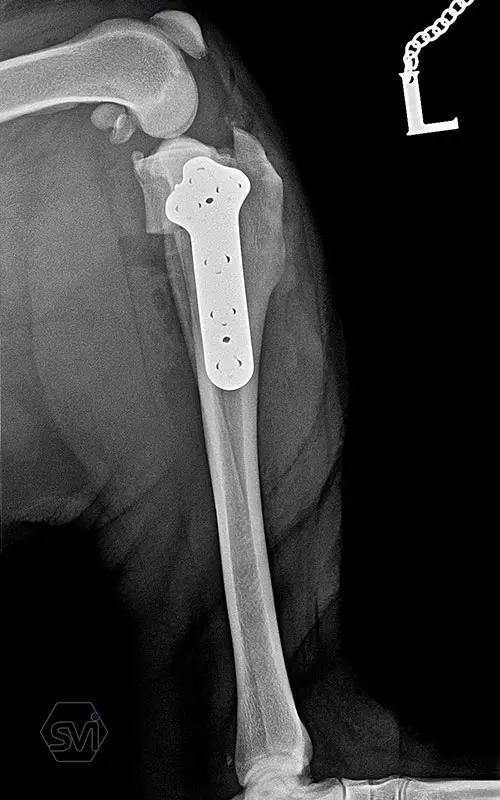

The precontoured polyaxial locking TPLO family has become complete in the smartvetimplants.com offer

Introducing the precontured polyaxial locking TPLO family, now available in all sizes:

- Mini: 2.0mm (thinner and thicker version)

- Midi: 2.4mm

- Small: 2.7mm

- Standard: 3.5mm (both in short and extended versions)

- Giant: designed for 4.0mm screws.

It has a number of advantageous features that make it stand out from standard TPLO solutions:

- well designed that follows the anatomical position and ideal hole placement

- precontoured, its use shortens the surgical time, no greater physical force is required for bending

- locking system for greater stability

- polyaxial screw insertion, the direction of screw insertion can be freely selected in a 30-degree circle while maintaining angular stability! (this is very useful to avoid driving the screw into the joint, and the temporary fixing can also be avoided with a K-wire)

- outstanding quality product, made in EU, in Hungary, and holds its own on both the European and American markets.